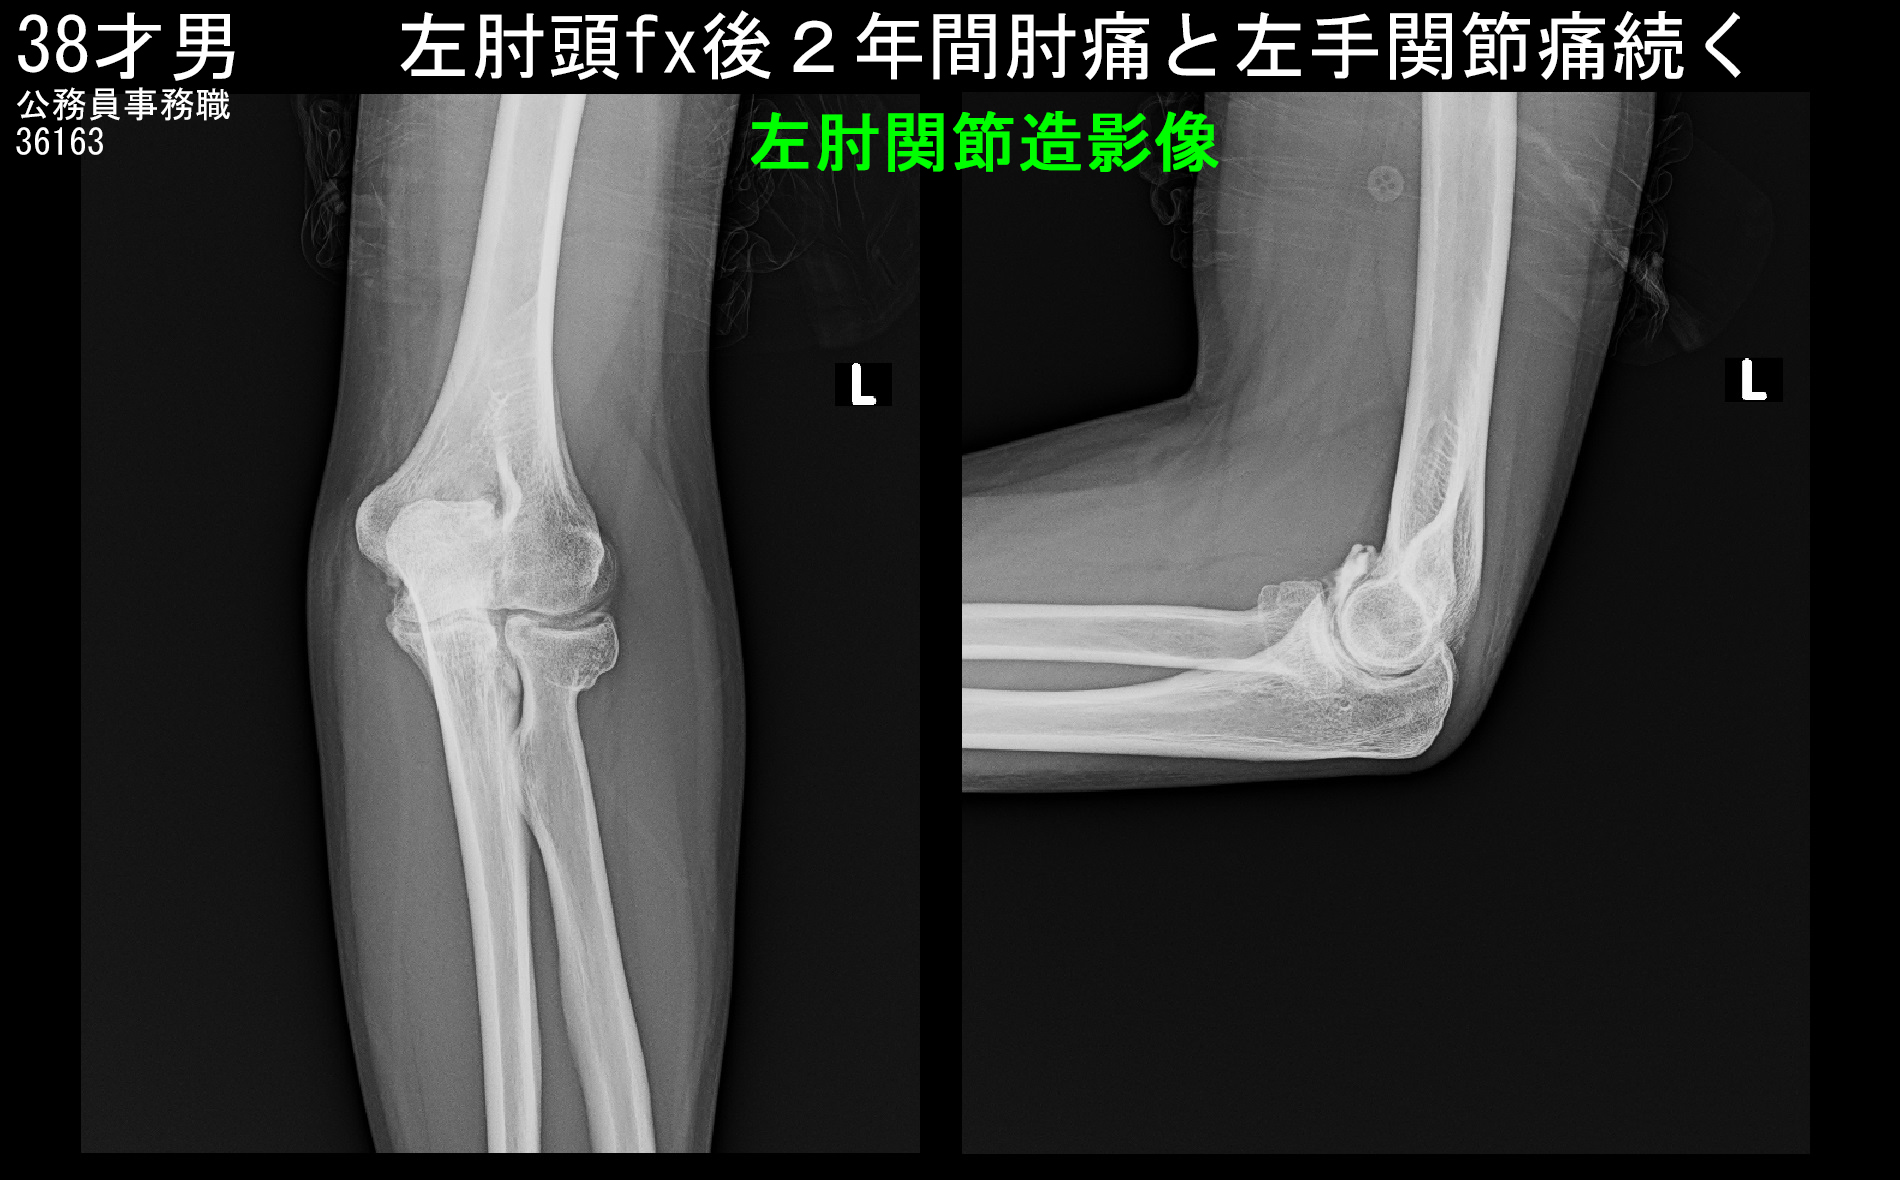

38才男 初診時Xp.jpg

初診時の左肘のレントゲン像です。左肘頭部とはオレンジ丸の領域ですが、異常を認めません。右肘に比して赤矢印の橈骨頭部と呼ばれる部分は左肘では四角く出っ張っていて、骨のラインは滑らかな曲線となっていません。この部分(橈骨頭部)に骨折があったと推察されます。橈骨頭部の骨折では手関節痛を訴えることはしばしばあります。